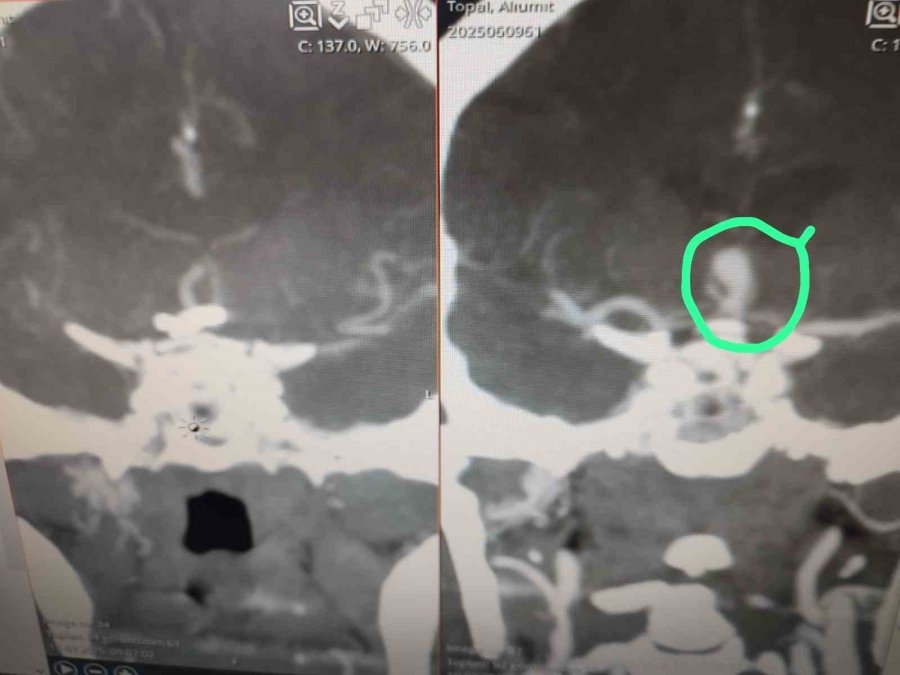

Beyninde anevrizma tespit edilen hasta, Serik Devlet Hastanesi'nde kaş üzerinden minimal bir kesi ile gerçekleştirilen operasyonla sağlığına kavuştu. Beyin ve sinir cerrahisi uzmanları Op. Dr. Ömer Elçik ve Op. Dr. Salim Tekir tarafından uygulanan yeni yöntem sayesinde hastanın ameliyat sonrası sürecinin hem daha konforlu geçtiği hem de estetik açıdan iz bırakmadığı bildirildi. Geleneksel beyin cerrahisinde kullanılan geniş kesiler yerine uygulanan modern teknik, özellikle yüz bölgesinde iz kalmasını istemeyen hastalar için önemli bir gelişme olarak değerlendiriliyor. Operasyonun ardından hasta kısa sürede taburcu edildi.